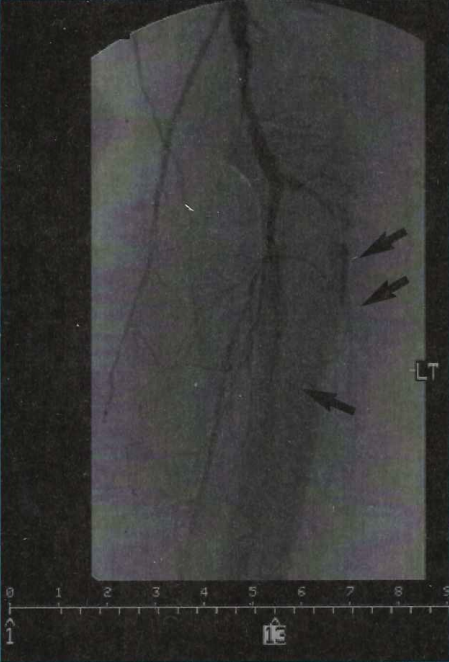

Case 4. A 13-year-old male was admitted due to fever and uncontrolled diarrhea and was then transferred to our institution after presenting with no pulse in both of his legs. His past medical history included having nephrotic syndrome. He was acidotic and lethargic; he did not move his legs and had no sensation. After an Allen’s test was performed via a right radial approach, emergency thoracic and abdominal arteriograms revealed total bilateral iliofemoral occlusions. A 6 Fr Oasis catheter (Boston Scientific/Medi-tech, Natick, Massachusetts) was inserted, and percutaneous mechanical thrombectomy (PMT) followed by PAT in the smallest vessels were performed bilaterally all the way down to the popliteal and tibial arteries. Intra-arterial urokinase drip via a 2.3 Fr Rapid Transit Catheter (Cordis Corp., Miami Lakes, Florida) placed in the abdominal aorta from a right radial artery approach was commenced, and heparin was continued intravenously. After 24 hours, some improvement in both legs was observed. However, the acidosis continued and the patient went into renal failure requiring dialysis, followed by multiorgan failure. Unfortunately, the patient died 4 days after the treatment. No autopsy was performed.

Catheterization technique. The procedures were performed under general endotracheal anesthesia or sedation. After arterial access was established, an additional bolus of heparin sulfate (50–100 IU/kg) was given, and the intravenous (IV) drip was adjusted if the aPTT was not adequate. All patients were maintained on IV heparin sulfate during the acute phase and were later changed to enoxaparin subcutaneously for the duration of their hospitalization. Initial angiograms of the affected areas were performed using a 4 Fr pig-tail catheter (Cordis) by power injection, or using a 4 Fr Benson-Hanafee-Wilson-1 (JB-1) (Terumo Corp., Natick, Massachusetts) by hand-injection of contrast. After localization of the affected vessel, an initial bolus of urokinase 4400 U/Kg or t-PA 0.9 mg/kg over 10 minutes was administered intra-arterially to all of the patients. The thrombolytic was chosen arbitrarily based on its availability at our institution at the time of presentation. After giving the medication, PAT was performed in all patients, as described by others.4 However, variations from the previously-described technique were employed based on the location and the catheter’s ability to reach the clot. A 6 Fr Oasis catheter (Boston Scientific/Medi-tech) was used, and thrombectomy was performed bilaterally all the way down to the popliteal arteries only in Case 4 due to the advantage of his size. Nitroglycerin boluses at 1–2 µg/kg were given intermittently every 5–10 minutes throughout the procedures if vasoconstriction occurred due to catheter manipulation and if no hypotension followed. The total duration of treatment (days) with urokinase or t-PA was based on the patients’ arteriograms and clinical improvement. At the same time, complications with the urokinase were kept at a minimum by monitoring fibrinogen levels and other clotting factors, which needed to be stopped in 1 case. In areas the catheters were unable to reach, a 0.014 inch guidewire (Guidant Corp., Santa Clara, California) was advanced in an attempt to break the clot and allow more thrombolytic agent to reach the distal aspects of the obstruction. When the removal of the clot was considered adequate, a 2.3 Fr Rapid Transit catheter (Cordis) was placed in a proximal aspect of the main arterial supply of the affected extremity, and the rest of the thrombolytic medication was given. In those who received urokinase, the medication was continued for 48–72 hours as a continued intra-arterial infusion at a rate of 4400 U/Kg/hour. Fibrinogen levels were monitored and maintained at approximately 100–150 mg/dl, with adjustments in the urokinase drip as needed. Results were analyzed by arteriography, and PAT was performed at that time if deemed necessary. In Cases 1 and 2, the urokinase drip was restarted after the second procedure and PTA was continued for an additional 48–72 hours. In Cases 3 and 4, after completing the total dose of t-PA, an intra-arterial infusion of nitroglycerin at a dose of 0.25 µg/kg/minute was continued for 48 hours. Nitroglycerin paste (1 to 3 inches, depending of the area) was rubbed over the affected limb of all the patients. Blood pressure was strictly monitored. The patients’ aPTT was monitored and maintained at approximately 2–2.5 times their initial level. The patient in Case 1 underwent a third arteriogram along with PTA and urokinase was continued for another 24 hours.

All of the patients tolerated the procedures without problems. One patient underwent 3 arteriograms and interventions (PAT) with concomitant administration of urokinase for a total of 7 days of intra-arterial treatment. Three underwent 2 interventions, 1 was treated with urokinase for 4.5 days, and the other 2 were given 2 doses of t-PA 2 days apart (Cases 3 and 5). In Case 3, intra-arterial nitroglycerin was restarted after the second treatment with t-PA and maintained for 72 hours more before discontinuing it. Case 4 underwent only 1 procedure and was given urokinase. In all the patients, repeat angiography revealed that the occlusions were not totally resolved after their previous interventions. For that reason, repeat PAT was performed on these patients. In the distal areas the catheters were unable to reach, we advanced a 0.014 inch guidewire to create a track for the medication. We noticed that the medication was able to clean the areas up to where the catheters or wires were advanced, but not further than that. All surviving patients were continued on enoxaparin sodium 1.5 mg/kg subcutaneously every 12 hours for 6 months.